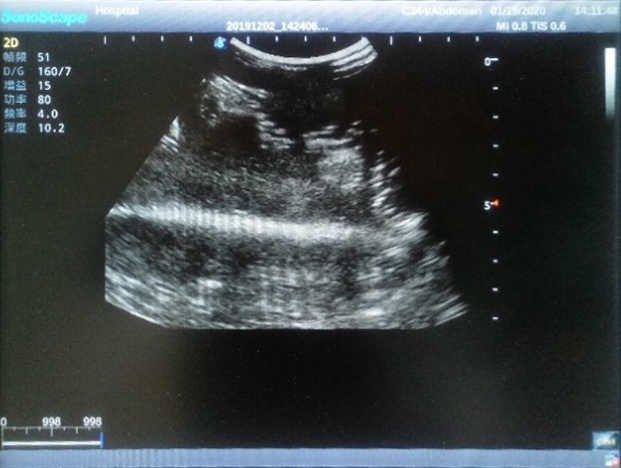

Outline

The Wearable Breast Ultrasound Examination Model allows users to develop and practice the skills necessary to gain proficiency in breast palpation, using ultrasound for normal and abnormal imaging and biopsy. It simulates adult female breasts with realistic size and appearance.

2)  Each model contains 8 space-occupying lesions of varying sizes, different in touch, elasticity and ultrasonogram

4) Biomimetic material allowing users to see clear and real normal tissues and space-occupying lesions that are hyperechoic, hypoechoic and isoechoic as they would see in the clinical environment